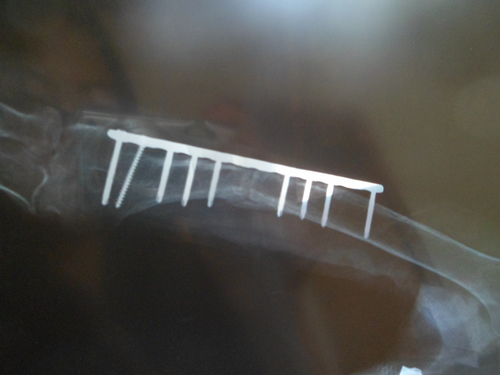

鋼釘明顯打在骨縫里,且斷裂兩顆

二次手術(shù)后基本愈合

????一顆鋼釘打進(jìn)骨接縫處

????“這要是不檢查還不知道,我看到給我父親拍的X光片,竟然有一根鋼釘打進(jìn)了骨頭斷裂的接縫處?!壁w女士氣憤地向記者說道,她找到當(dāng)時(shí)的主治醫(yī)生想問個(gè)究竟,結(jié)果醫(yī)院表示胳膊沒有愈合和鋼釘沒有關(guān)系。趙女士拿出當(dāng)時(shí)給她父親拍的X光片,對(duì)記者說,“你看這是第一次手術(shù)后去醫(yī)院檢查時(shí)拍的片子,胳膊上的鋼板總共釘了9顆鋼釘,有兩顆已經(jīng)斷了,還有一顆明顯是打進(jìn)骨頭的接縫的地方了。”

????據(jù)趙女士介紹,當(dāng)時(shí)家里人不能認(rèn)同醫(yī)院的說法,就要求醫(yī)院對(duì)這件事進(jìn)行處理,并賠償她父親的精神和身體上所受到的傷害。“當(dāng)時(shí)我們決定帶父親到其它醫(yī)院做二次手術(shù),但是醫(yī)院不同意,結(jié)果醫(yī)院請(qǐng)專家為我父親免費(fèi)做二次手術(shù)。”趙女士說道,關(guān)于賠償?shù)葐栴}到二次手術(shù)結(jié)束后在做處理。在2010年9月份,市立醫(yī)院從文登整骨醫(yī)院請(qǐng)來整骨專家謝波為她父親做了二次手術(shù)。